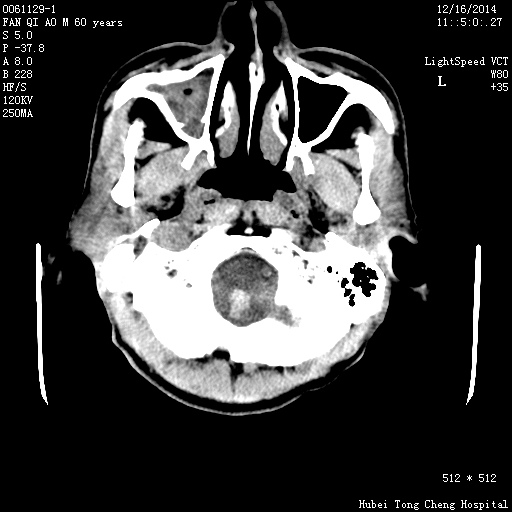

CT49579:M,60Y。昏迷2小时。

【结果公布】 患者,男,60岁。昏迷2小时。 临床诊断:昏迷原因待查:脑血管意外? 头部CT轴位平扫,图像如下:(请注意大脑镰与血肿之间的是什么) &nbs ...

左侧额顶叶见梭形高密度影,其边界清楚密度尚均匀,周围环绕低密度水肿带,近顶部见基底位于大脑镰半园形稍低密度影,左侧脑室及大脑镰受压右移,脑室系统内见高密度影填充,考虑:脑膜瘤伴出血并破入脑室系统及大脑镰下疝形成。

1、左额叶脑出血破入脑室系统。

2、额部镰旁脑膜瘤。

左侧顶叶及基底节血肿,破入脑室。右上颌窦炎症。

1、左侧额顶叶出血并破入脑室系统

2、大脑镰疝形成

左额叶脑出血破入脑室系统。

额部镰旁占位

1左侧额叶出血,破入脑室。2桥脑出血?3脑膜瘤?建议头部MRI